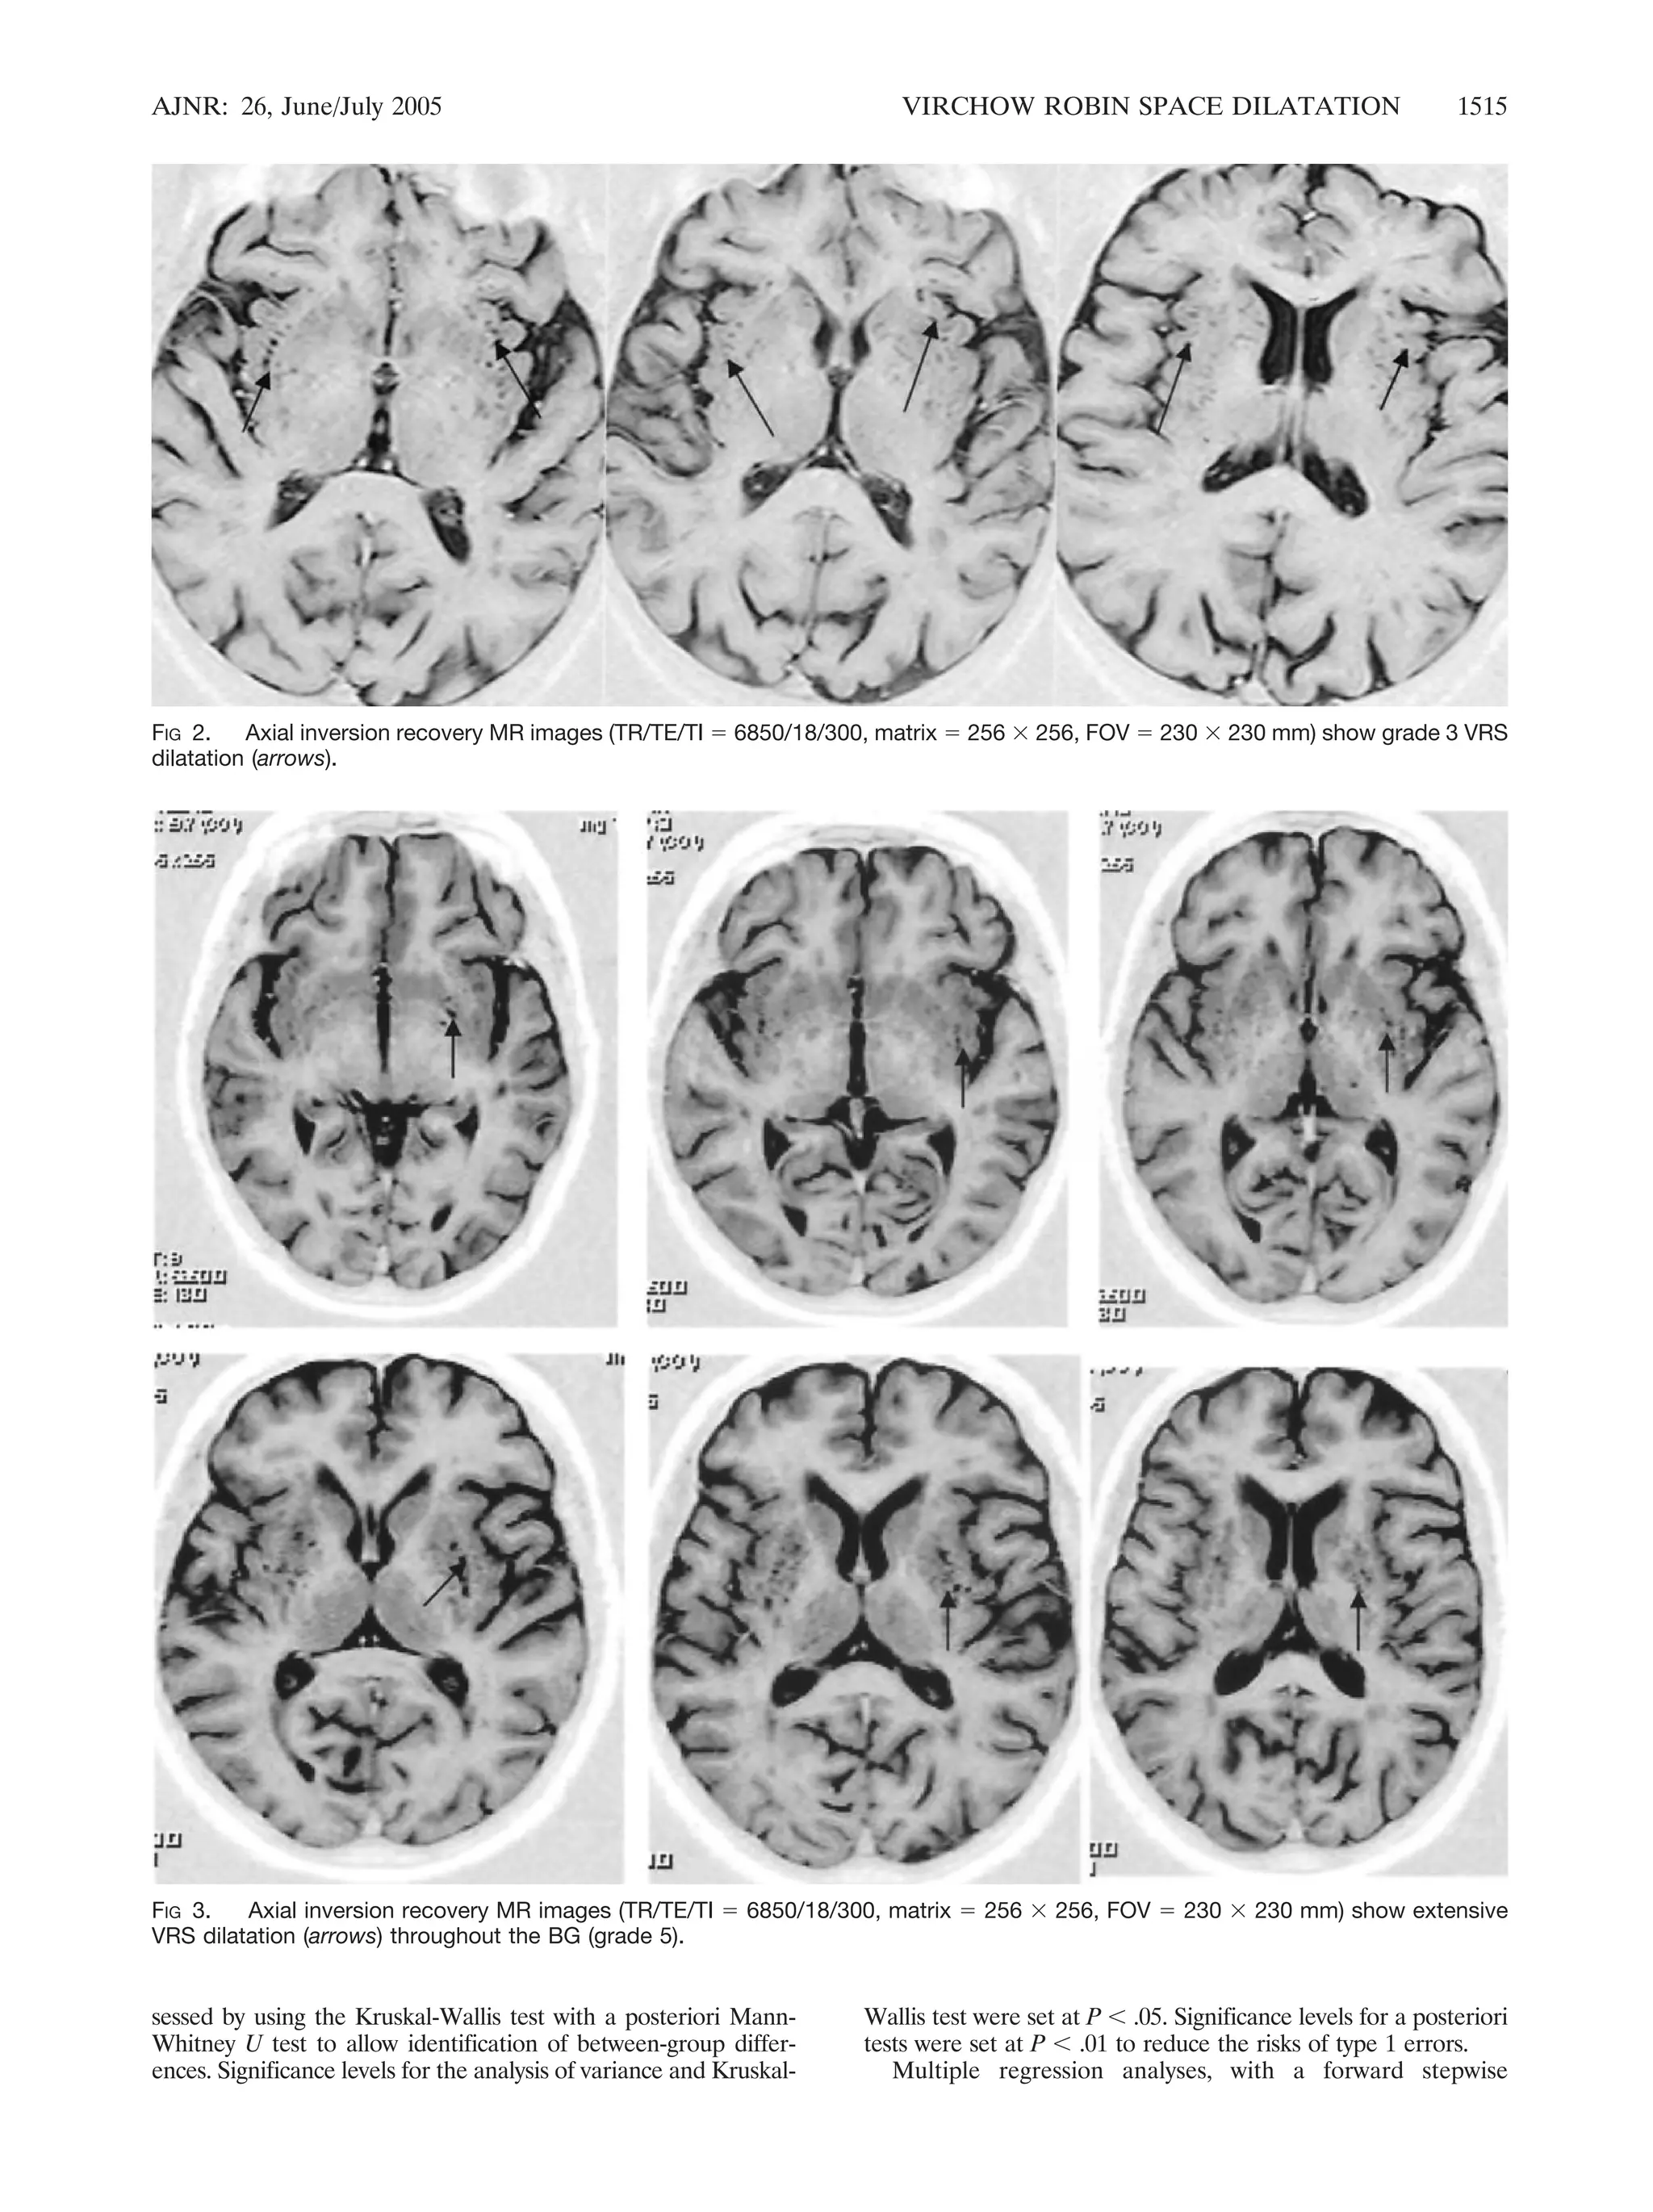

FIG 2. Axial inversion recovery MR images (TR/TE/TI  6850/18/300, matrix  256  256, FOV  230  230 mm) show grade 3 VRS

dilatation (arrows).

FIG 3. Axial inversion recovery MR images (TR/TE/TI  6850/18/300, matrix  256  256, FOV  230  230 mm) show extensive

VRS dilatation (arrows) throughout the BG (grade 5).

caudate nucleus on either side. BG scheme 2 was as follows:

0  VRS present only in the substantia innominata and fewer

than five VRSs on either side, 1  VRS only in the substantia

innominata or more than five dilated VRS on either side, 2

fewer than five in the lentiform nucleus on either side, 3  five

to 10 VRSs in the lentiform or fewer than five in the caudate

nucleus on either side (Fig 2), 4  more than 10 in the

lentiform nucleus and fewer than five in the caudate nucleus on

either side, 5  more than 10 in lentiform nucleus and more

than five in the caudate nucleus on either side (Fig 3).